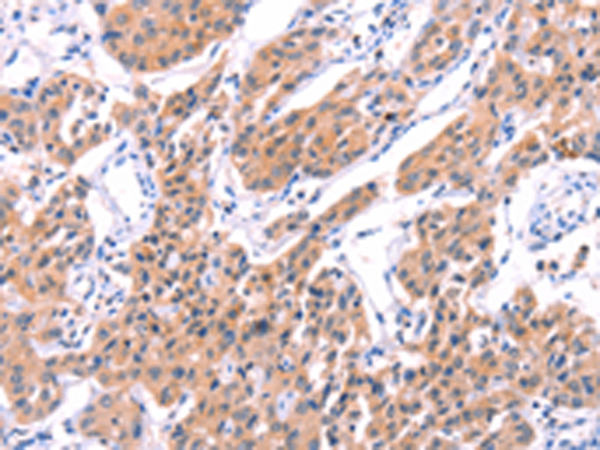

分类: 科研抗体货号: P07714别名: PSA; PROS; PS21; PS22; PS23; PS24; PS25; THPH5; THPH6应用: IHC反应种属: Human